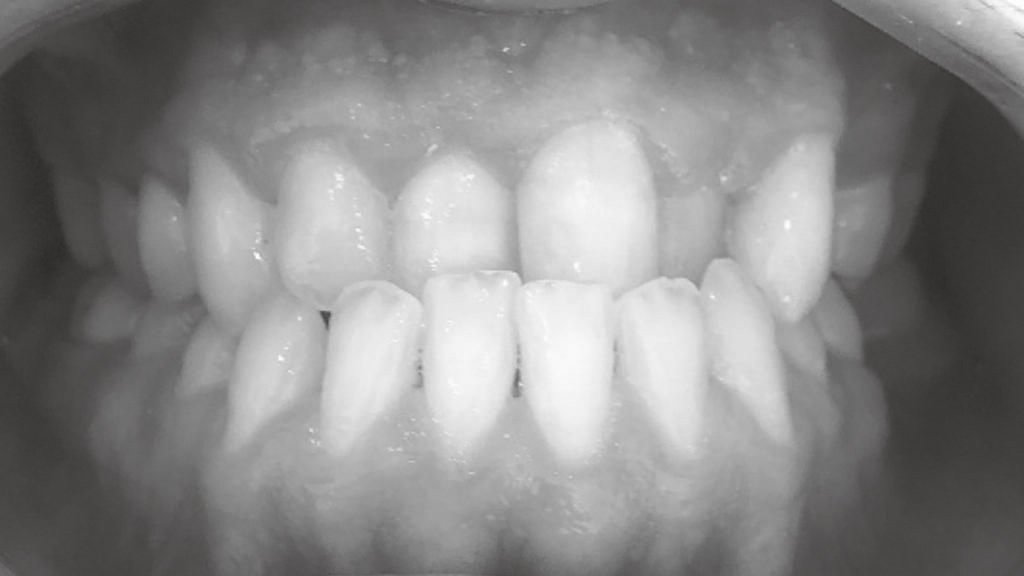

Antes y después en nuestros tratamientos dentales

A continuación te exponemos algunos de nuestros casos de antes y después en implantes dentales, ortodoncia y estética dental.

Antes y después en Blanqueamiento Dental

En un blanqueamiento dental el cambio es sorprendente y la sonrisa se ve rejuvenecida y más atractiva. Gracias a la lámpara Philips ZOOM!, la más avanzada del mercado, el proceso de blanqueamiento es seguro y con resultados duraderos. Se pueden lograr resultados significativamente más eficaces que con los productos de blanqueamiento en el hogar.